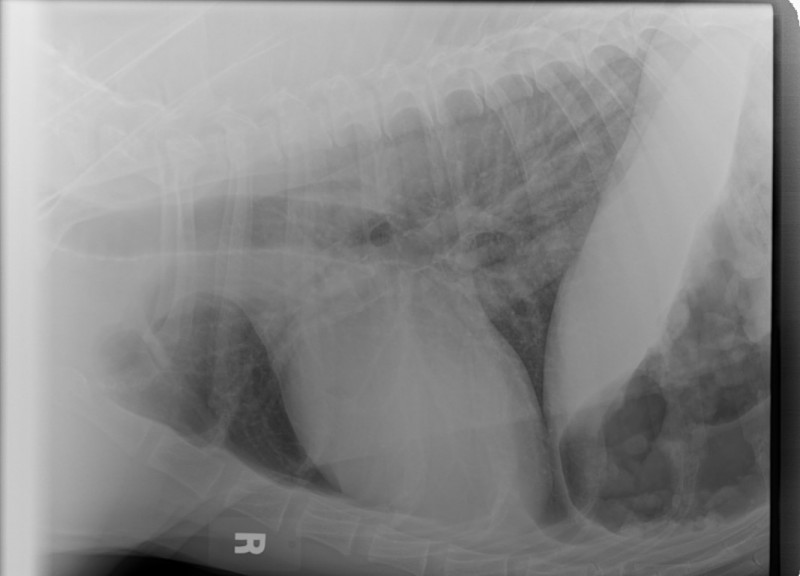

Below is a photo of the one mass……the one that was removed.

The first picture of her mouth with the second mass, after the first mass(in photo below in jar was removed), the puncture biopsy was done on the second mass and, the sutures were placed.

You can see where the first mass was removed also.

If you click on the photo, you can see it enlarged….